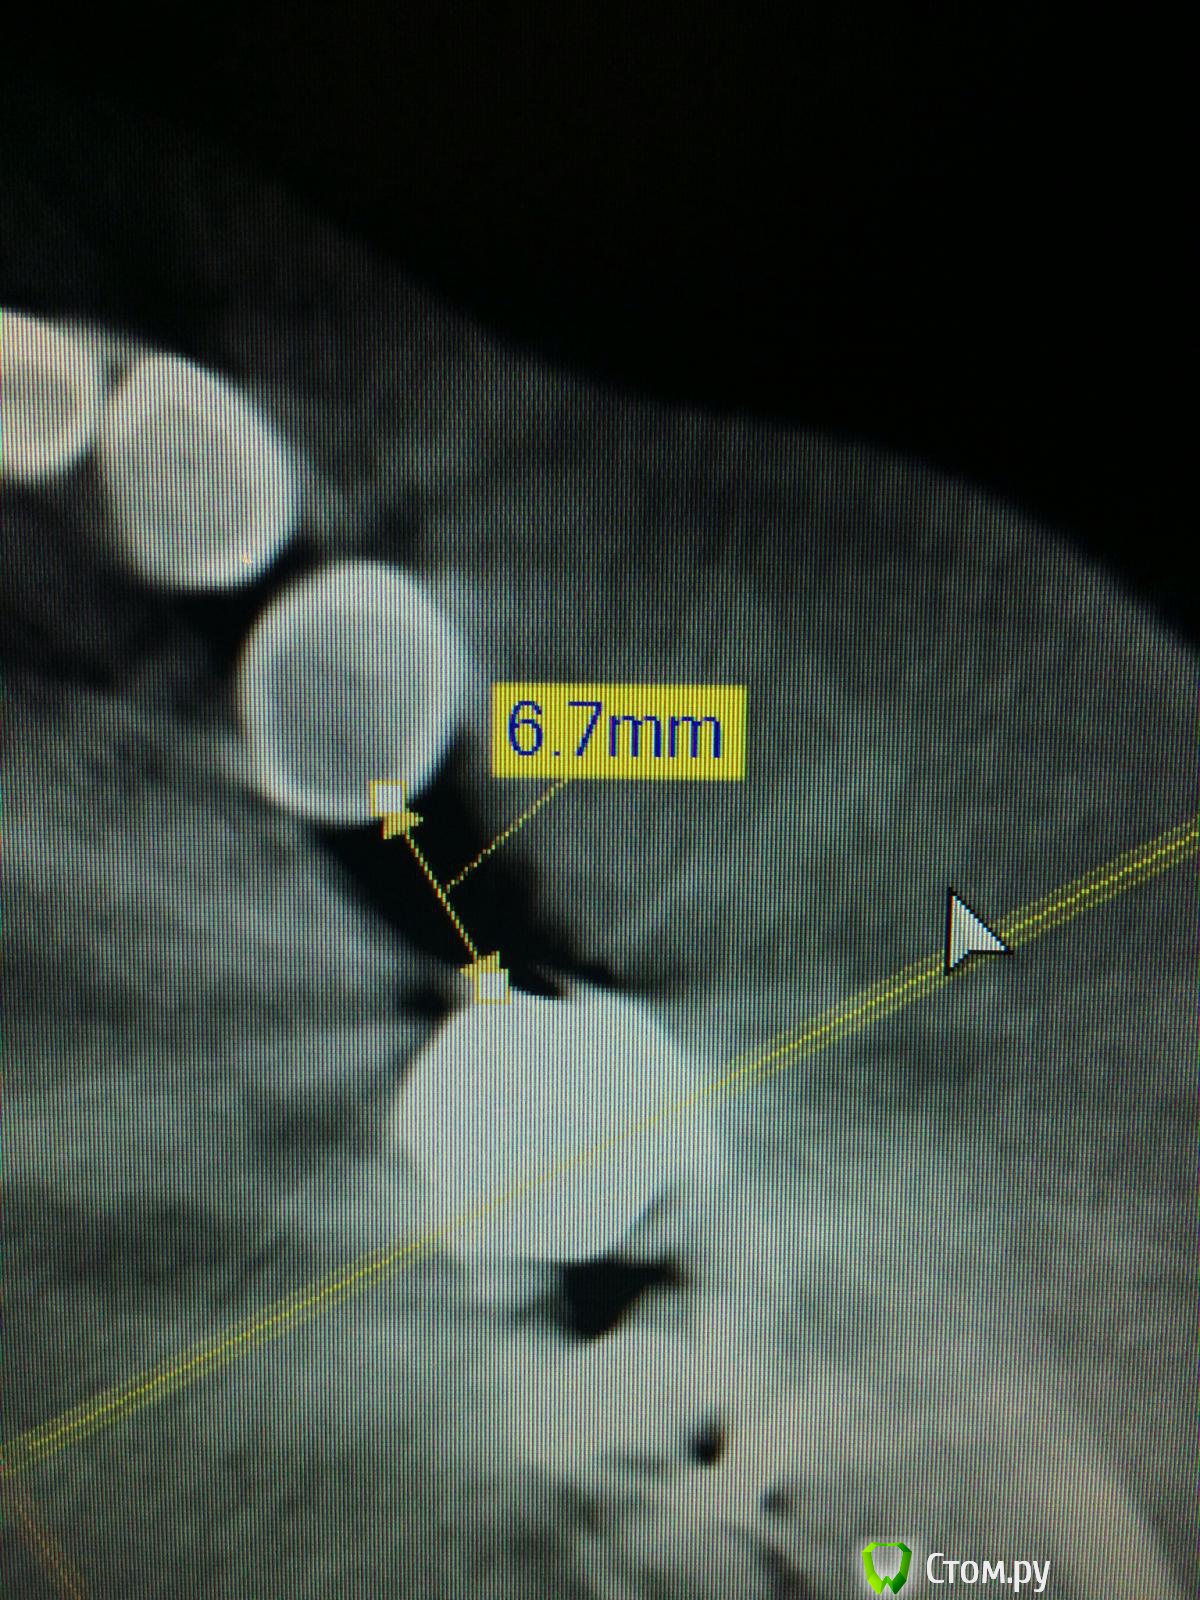

Vadim09 Опубликовано 3 октября, 2014 Поделиться Опубликовано 3 октября, 2014 (изменено) В области 3.5 отсутствует зуб, планирую поставить имплантиум 3.8, с расщеплением и подсадкой кости мис 4bone и мембраной от мис, подскажите тонкости, чтобы не сделал ошибку и простите, если вопрос не корректный. Изменено 3 октября, 2014 пользователем Vadim09 Ссылка на комментарий

doc-евгений Опубликовано 4 октября, 2014 Поделиться Опубликовано 4 октября, 2014 Имплантат 3.6 с нкр, без расщепления. Гребень с поднутрением, большая вероятность отлома. Ссылка на комментарий

k.t.m. Опубликовано 4 октября, 2014 Поделиться Опубликовано 4 октября, 2014 Спасибо, воспользовался вашим советом, кортикалка лопнула у шейки немног, пдсыпал биоосса и покрыл мембранойimage.jpgimage.jpgнадо было заглубить и более медиальнее 3 Ссылка на комментарий